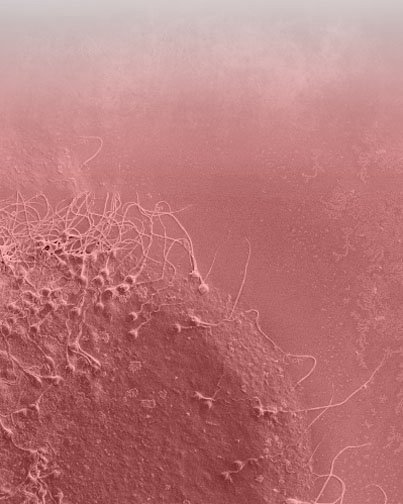

RESEARCH GIVES US LIFE

We help you to form a family